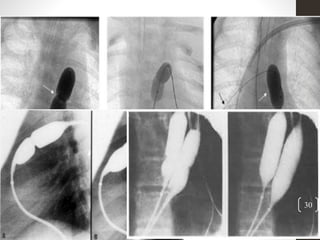

Balloon position and dilation

• Lateral angiogram to be kept as reference.

• Balloon is centered onto the valve and inflated to 6 atm.

• Balloon movement during inflation is common so the catheter must be

maintained in position and the inflation recorded so that it may be

reviewed.

• If no complete resolution of the balloon waist – reposition and the

inflation to be repeated.

• Following dilation the balloon catheter to be exchanged for the wedge

catheter and right heart pull back hemodynamic pressure

measurements to be repeated.

• RV angiogram in AP and lateral projections – dynamic RVOT

stenosis, aneurysm formation or new onset TR..

• Dynamic obstruction will resolve gradually.